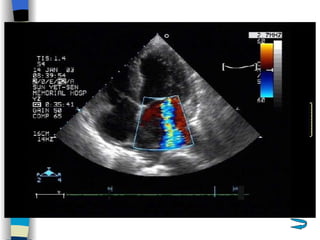

Echocardiography The most valuable technique for diagnosing MS, and determining its severity M-mode echo : Thickened, calcified leaflets open poorly, close slowly (EF slope ↓ ) The double peaks disappear Both leaflets move anteriorly during early diastole Two-dimensional echo: Fusion, thickening,  doming  of the valve leaflets, and poor leaflet separation in diastole;  mitral orifice area ↓

Doppler echo : Most accurate noninvasive technique for quantifying the severity of MS Spectrum Doppler: measure transvalvular gradient, MVA Color Doppler: display  high velocity color jet Provide other important information Cardiac chamber size (LA, RV) Left ventricular contractility Pulmonary arterial pressure Other coexisted valvular or congenital abnormalities  Mural thrombi

Echocardiography 1 、 Display anatomy of the mitral valve apparatus Useful in determining the etiology of MR ( 2D ) 2 、 Confirm the existence of MR Doppler   (color, spectrum): reveal high-velocity jet into LA during systole Sensitivity~100% Estimate the severity of MR < 4 cm2  Mild ( Color flow jet area )  4~8 cm2  Moderate  > 8 cm2  Severe 3 、 Measure cardiac chamber sizes, evaluate LV function, pulmonary artery pressure, provide data concerning other valvular lesions

Echocardiography The mostvaluable technique for diagnosing MS, and determining its severity M-mode echo : Thickened, calcified leaflets open poorly, close slowly (EF slope ↓ ) The double peaks disappear Both leaflets move anteriorly during early diastole Two-dimensional echo: Fusion, thickening, doming of the valve leaflets, and poor leaflet separation in diastole; mitral orifice area ↓

Doppler echo :Most accurate noninvasive technique for quantifying the severity of MS Spectrum Doppler: measure transvalvular gradient, MVA Color Doppler: display high velocity color jet Provide other important information Cardiac chamber size (LA, RV) Left ventricular contractility Pulmonary arterial pressure Other coexisted valvular or congenital abnormalities Mural thrombi

Echocardiography 1 、Display anatomy of the mitral valve apparatus Useful in determining the etiology of MR ( 2D ) 2 、 Confirm the existence of MR Doppler (color, spectrum): reveal high-velocity jet into LA during systole Sensitivity~100% Estimate the severity of MR < 4 cm2 Mild ( Color flow jet area ) 4~8 cm2 Moderate > 8 cm2 Severe 3 、 Measure cardiac chamber sizes, evaluate LV function, pulmonary artery pressure, provide data concerning other valvular lesions